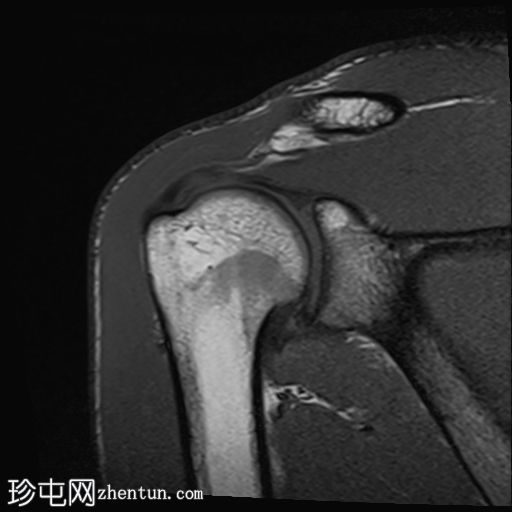

轴位PD序列

脂肪抑制序列

肱骨头后外侧骨缺损,伴有骨髓挫伤,符合近期肩关节前脱位引起的急性Hill-Sachs损伤。

前下盂唇撕脱,骨膜附着完整,提示软性Bankart损伤。

肩胛盂下韧带前束在盂肱关节附着处断裂,符合GAGL(肩胛盂下韧带)的特征,盂肱关节下方可见关节囊外积液,并伴有盂唇旁囊肿。